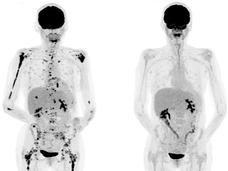

FDA Approves Pembrolizumab for Tumors with Specific Genetic Features

FDA approved pembrolizumab for patients with solid tumors that have specific genetic features, called mismatch repair deficiency and high microsatellite instability. This is the first approval based on a genetic feature, rather than cancer type.